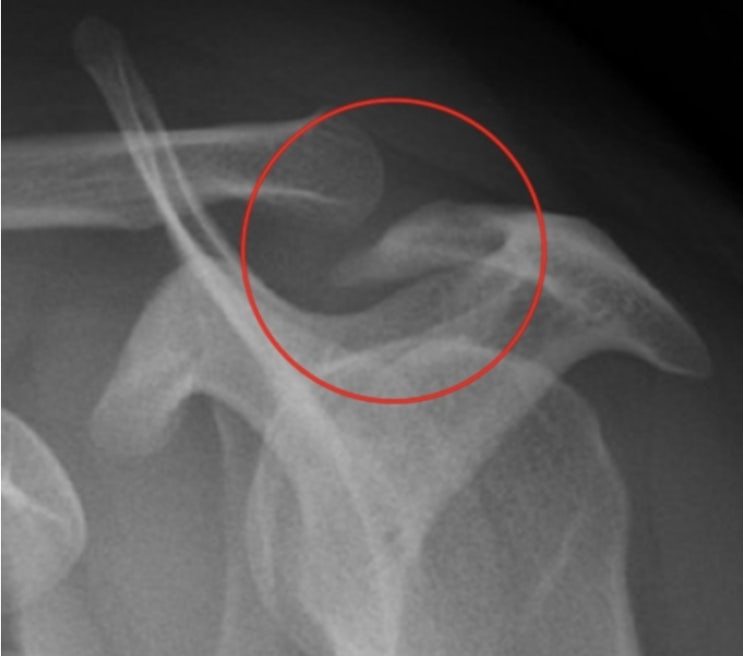

어깨 충돌 증후군에 걸렸어요

운동에 약간의 진심이 들어가고부터 조촐하게 부상(?) 이벤트가 매달 있네요. 이번 달은, 어깨 충돌 증후군...